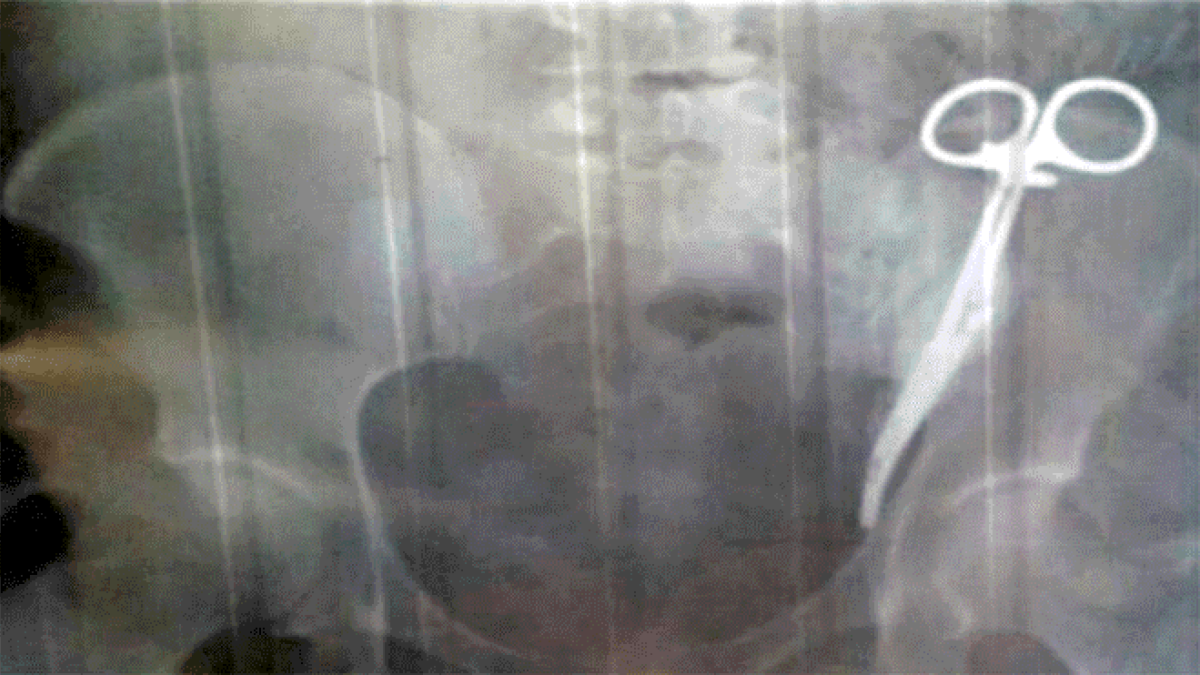

Ezeta decidió averiguar cuál era la causa de sus repetidos dolores y decidió hacerse una radiografía. Mientras la radióloga revisaba los resultados, pensó que la paciente tenía unas tijeras en el bolsillo, pero después descubrió que se trataba de un instrumento quirúrgico de 15 centímetros de largo, el cual estaba alojado en el abdomen de la mujer.

La radióloga llegó a pensar que se trataba de unas tijeras en el bolsillo de la mujer.